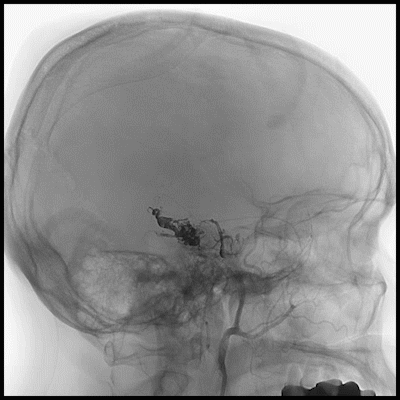

高流量瘘栓塞

深部供血栓塞

栓塞术后CT

DSA-R-ECA-脑膜中动脉

DSA-R-MCA-颞前动脉

DSA-R-VA-颞叶下动脉